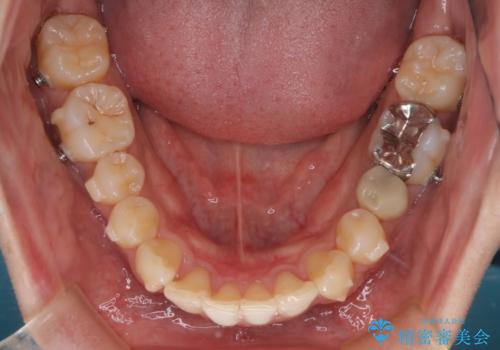

前歯のガタガタを治したい。

- 凸凹を治したいと来院された患者様です。

インビザラインにて、遠心移動を行いながら綺麗に配列することができました。